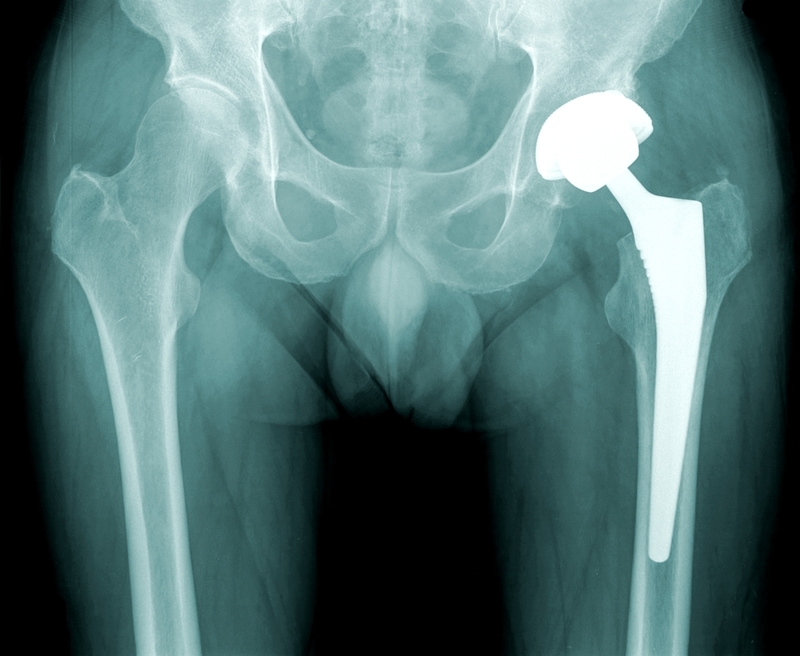

Doctors at Gujarat Cancer Research Institute (GCRI) have successfully operated on the femur bone of an 8-year old girl from Bhavnagar district, Gujarat, who was diagnosed with Ewing's sarcoma.

Doctors replaced her hip and knee joints together by replacing the entire bone. The girl underwent the surgery in December 2016 and has now completely regained use and control of her leg. Dr. Abhijit Salunke, bone cancer surgeon at GCRI mentioned that less than 100 such surgeries have been performed in India.